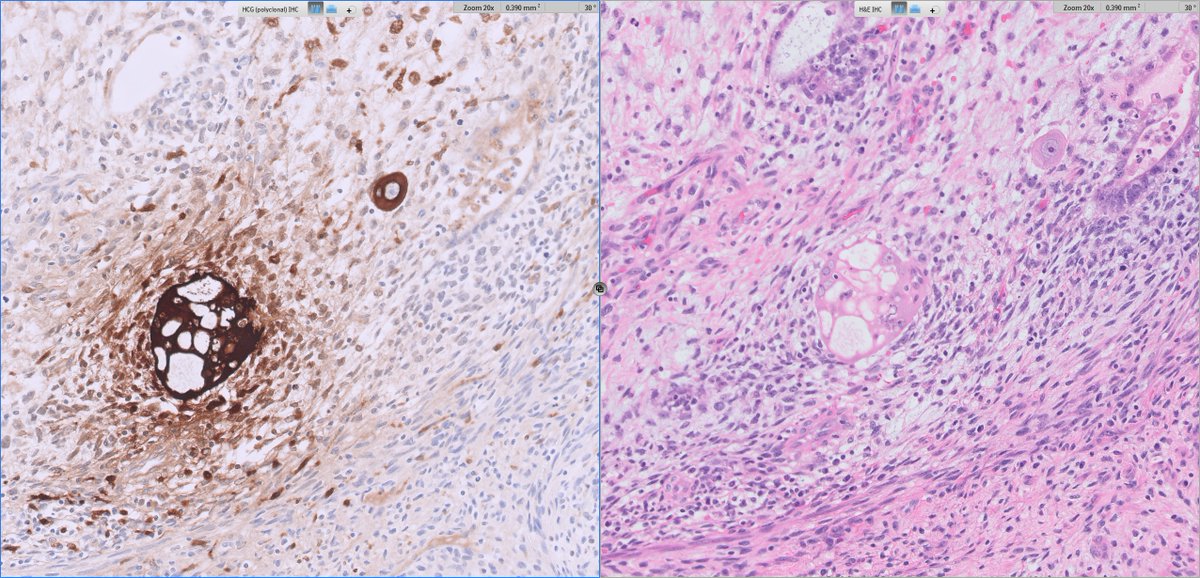

#GUpath orchiectomy:

mixed germ cell tumor (GCT) with admixed syncytiotrophoblasts

✔️may account for low serum elevations of HCG but NOT diagnostic of choriocarcinoma elements